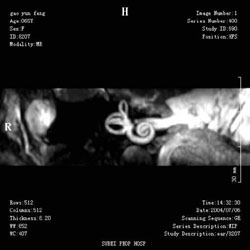

2.腎小管內能量代謝不足產生的能量難以支持正常轉運有些毒物或藥物中毒以及遺傳代謝疾病使某些代謝產物在腎小管內儲積過多影響了細胞內氧化磷酸化過程,ATP生成不足,沒有足夠的能量支持腎小管轉運物質無論什麼機制可最終導致多種物質轉運異常。范可尼綜合徵是近曲小管多項轉運缺陷病包括胺基酸葡萄糖鈉鉀、鈣磷碳酸氫鈉尿酸和蛋白質。原發性者近端小管呈天鵝頸樣變形。